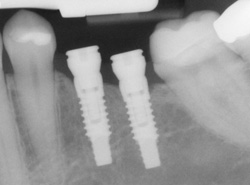

Implants are titanium screws that replace the roots of missing teeth. The implant restoration is the portion of the implant above the gum line. Unlike bridges, which may need to be replaced when teeth decay, or dentures, which are removable plastic teeth, implants allow for natural-looking and functioning teeth that remain in place 24/7.

The dental implant itself is only a replacement for the root of the lost tooth, so after the implant has been placed, you’ll still need to get a restoration, or replacement tooth, at our Windsor, CT dental office.

To make the new tooth or teeth, Dr. Garceau will make an impression of your existing teeth, creating a model of your bite. The new restoration, most typically a crown, will be based on this model so it will blend in perfectly with the rest of your teeth. The crown is then attached to the connector point (abutment) on your implant.